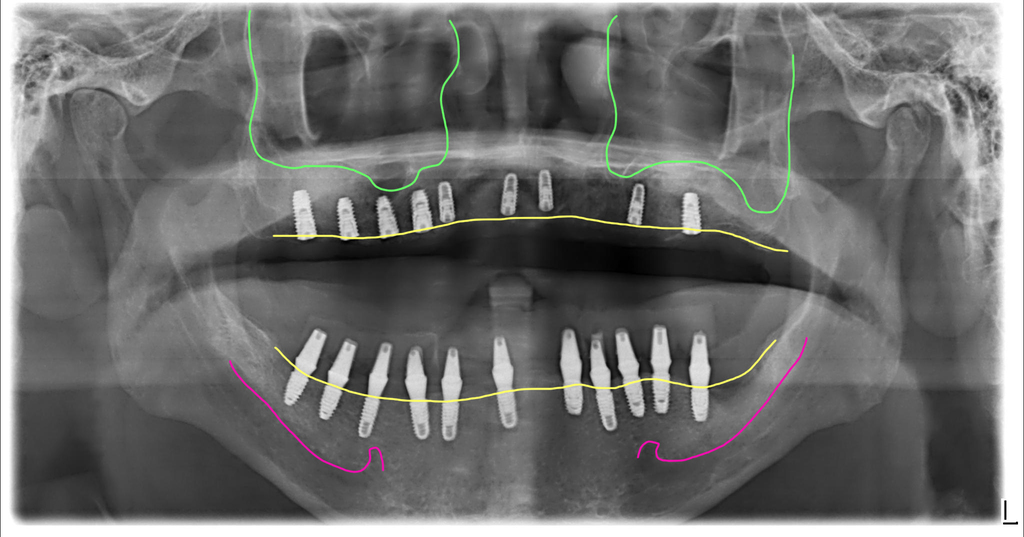

이 분은 아래가 너무 불편해서 윗쪽은 완전틀니를 사용하시면서 아래만 먼저 수술을 원해서 진행했어요. 브릿지와 치아를 제거하고 즉시임플란트를 11개 식립하고 지대주를 연결해서 임시치아를 만들어 드렸습니다.

환자가 원래 가지고 있던 상악의 틀니가 삐뚤어져 있어서 결국 5개월 뒤에 아래 보철을 하려고 할 때 밸런스를 맞추기 위해 윗니 전체임플란트를 결정하고 수술하셨어요.

최종완성 위아래 전체임플란트를 크라운 브릿지 방식으로 완성

이 분은 위아래 충분한 개수의 임플란트를 식립해서 자연치와 가장 유사한 형태의 보철인 크라운 브릿지 방식으로 치료를 마무리한 모습입니다.

현재 이 분은 6년째 별다른 문제없이 잘 사용하고 계시고 정기검진도 잘 받고 계세요.

아 그리고, 이 분은 하악골의 뼈가 너무 좁아서 네비게이션 수술이 꼭 필요했던 분이었어요. 보통 하악골은 이렇게까지 얇은 분은 드물지만 이렇게 좁고 딱딱한 뼈에는 더 많은 주의를 기울여서 수술을 해야 합니다.

치료전후 CT 비교사진입니다. 겨우 뼈 속에 임플란트를 위치시켜서 완성한 모습이에요. 네비게이션이 도움이 된 수술입니다.